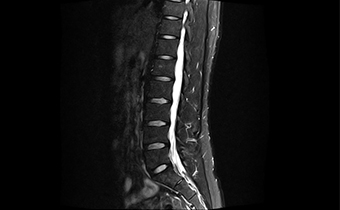

高均匀度磁体

呈现大FOV、偏中心优质图像;实现大范围压脂成像,缩短压脂序列时间